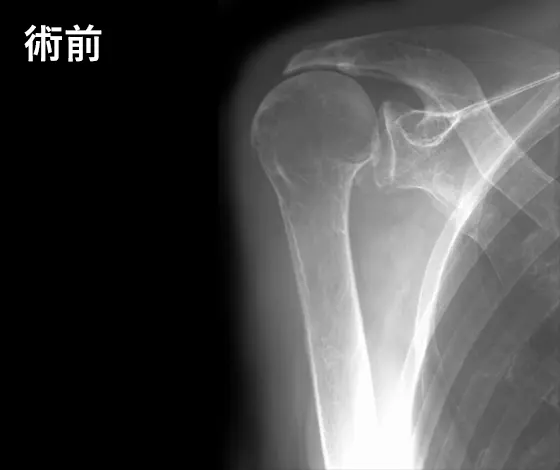

人工肩関節手術の例

人工肩関節手術の例:術前

腱板断裂性肩関節症

人工肩関節手術の例:術後